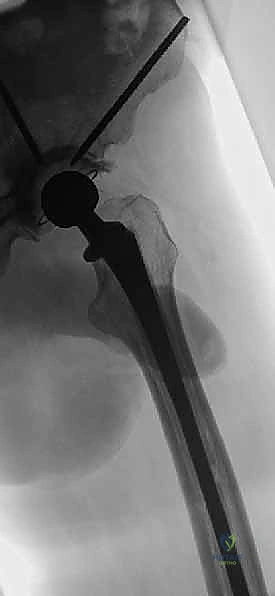

- اختيار نوع المفصل الاصطناعي: بناءً على صور الأشعة المقطعية، يحدد الجراح نوع المفصل. في حالات الأورام، غالباً ما تُستخدم مفاصل ذات جذوع طويلة (Long-stem prostheses) لتجاوز منطقة الورم وتثبيت المفصل في العظم السليم أسفل الآفة. كما تُستخدم تقنية الأسمنت العظمي (Bone Cement - PMMA) بكثافة لتوفير استقرار فوري للمفصل والسماح للمريض بالمشي في اليوم التالي.

الخطوة 3: إعادة بناء تجويف الحُق (Acetabular Reconstruction)

إذا كان الورم قد دمر تجويف الحوض، فإن هذه المرحلة تتطلب مهارة هندسية حيوية.

* يتم تنظيف التجويف وتوسيعه بآلات خاصة.

* إذا كان التدمير كبيراً، يستخدم الدكتور هطيف دعامات معدنية خاصة (Reconstruction Rings/Cages) يتم تثبيتها بمسامير في عظام الحوض السليمة لإنشاء سقف جديد للمفصل.

* يتم تثبيت الكوب البلاستيكي أو المعدني (Socket) باستخدام الأسمنت العظمي لضمان ثباته الفوري.

الخطوة 4: تحضير عظم الفخذ وتثبيت الجذع (Femoral Stem Insertion)

- يتم تجويف القناة النخاعية داخل عظم الفخذ لتتناسب مع حجم الجذع المعدني (Stem).

- في مرضى السرطان النقيلي، يُفضل استخدام الأسمنت العظمي لتثبيت الجذع. الأسمنت العظمي لا يعمل كصمغ فقط، بل كحشوة تملأ الفراغات التي تركها الورم وتوفر دعماً ميكانيكياً فورياً.

- يتم وضع رأس معدني أو خزفي (Ceramic Head) على قمة الجذع.

الخطوة 5: رد المفصل والاختبار

يتم إدخال الرأس الجديد في التجويف الجديد (Reduction). يقوم الدكتور هطيف باختبار المدى الحركي للمفصل في جميع الاتجاهات للتأكد من استقراره التام وعدم قابليته للخلع، والتأكد من تساوي طول الساقين.